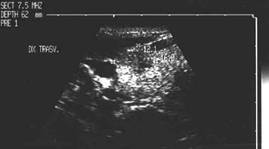

Lob drept, proiectie trasversala si longitudinala.

Femeie de 34 ani. Cunoscute cu hipertiroidism in

cadrul maladiei Graves.

Nodul paraistmic anterior dr. de 11x20x19mm (2 cc), cu margini nedefinite prin

absenta haloului periferic, neomogene, hipoecogen, care deformeaza conturul anterior

al glandei.

Examen citologic: carcinom papilar. Confirmare histologica (carcinom papilar multifocal cu metastaze linfonodale).